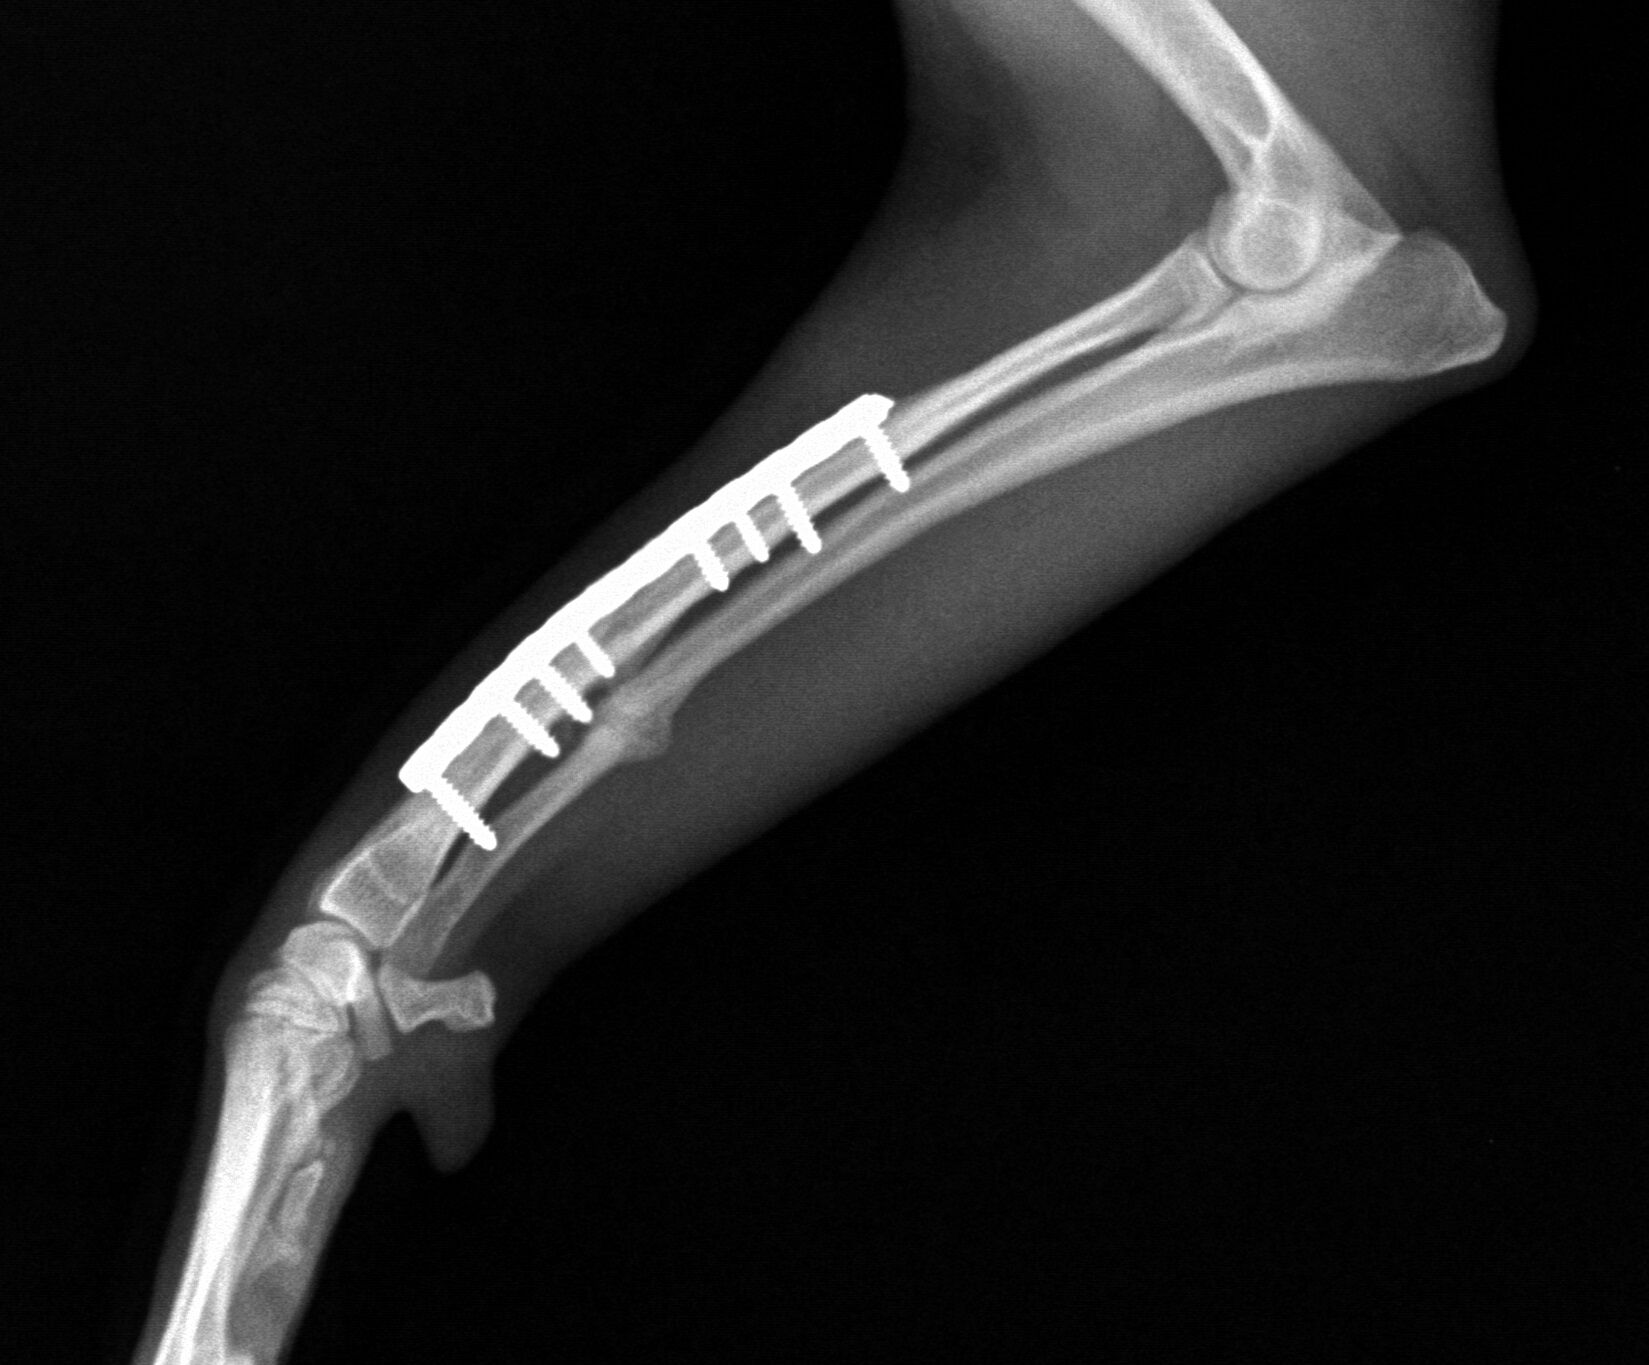

その夜、プレートにて内固定を行い、翌々日には外固定をして退院しました。

2か月後、レントゲン撮影を行い、骨折線が消えていたのでプレートを外して

治療終了しました。今では何の問題もなく元気にしています。

2か月後、